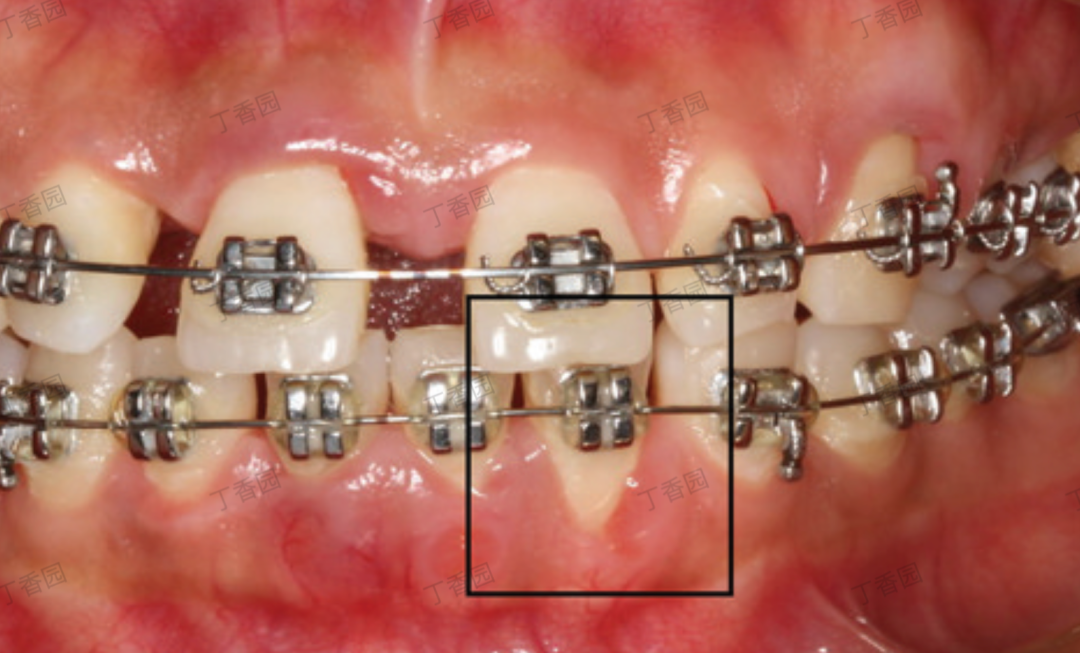

👉 不良修复体或正畸过程中拉太快:也可能产生压迫或刺激12]。

正畸牙移动与牙龈退缩

图片来源:丁香园